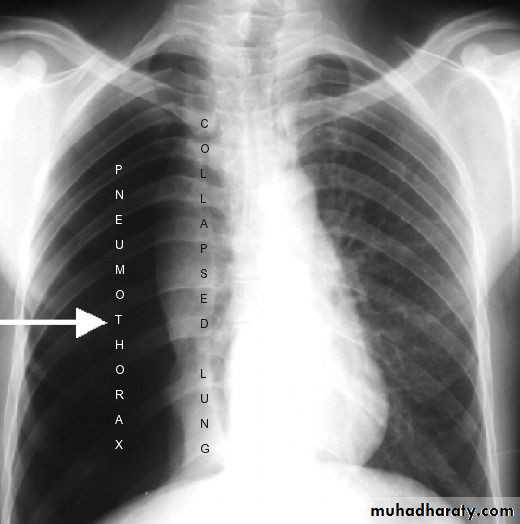

2- Compression atelectasis

results whenever significant volumes of fluid (transudate, exudate or blood), tumor, or air (pneumothorax) accumulate within the pleural cavity.With compression atelectasis, the mediastinum shifts away from the affected lung.